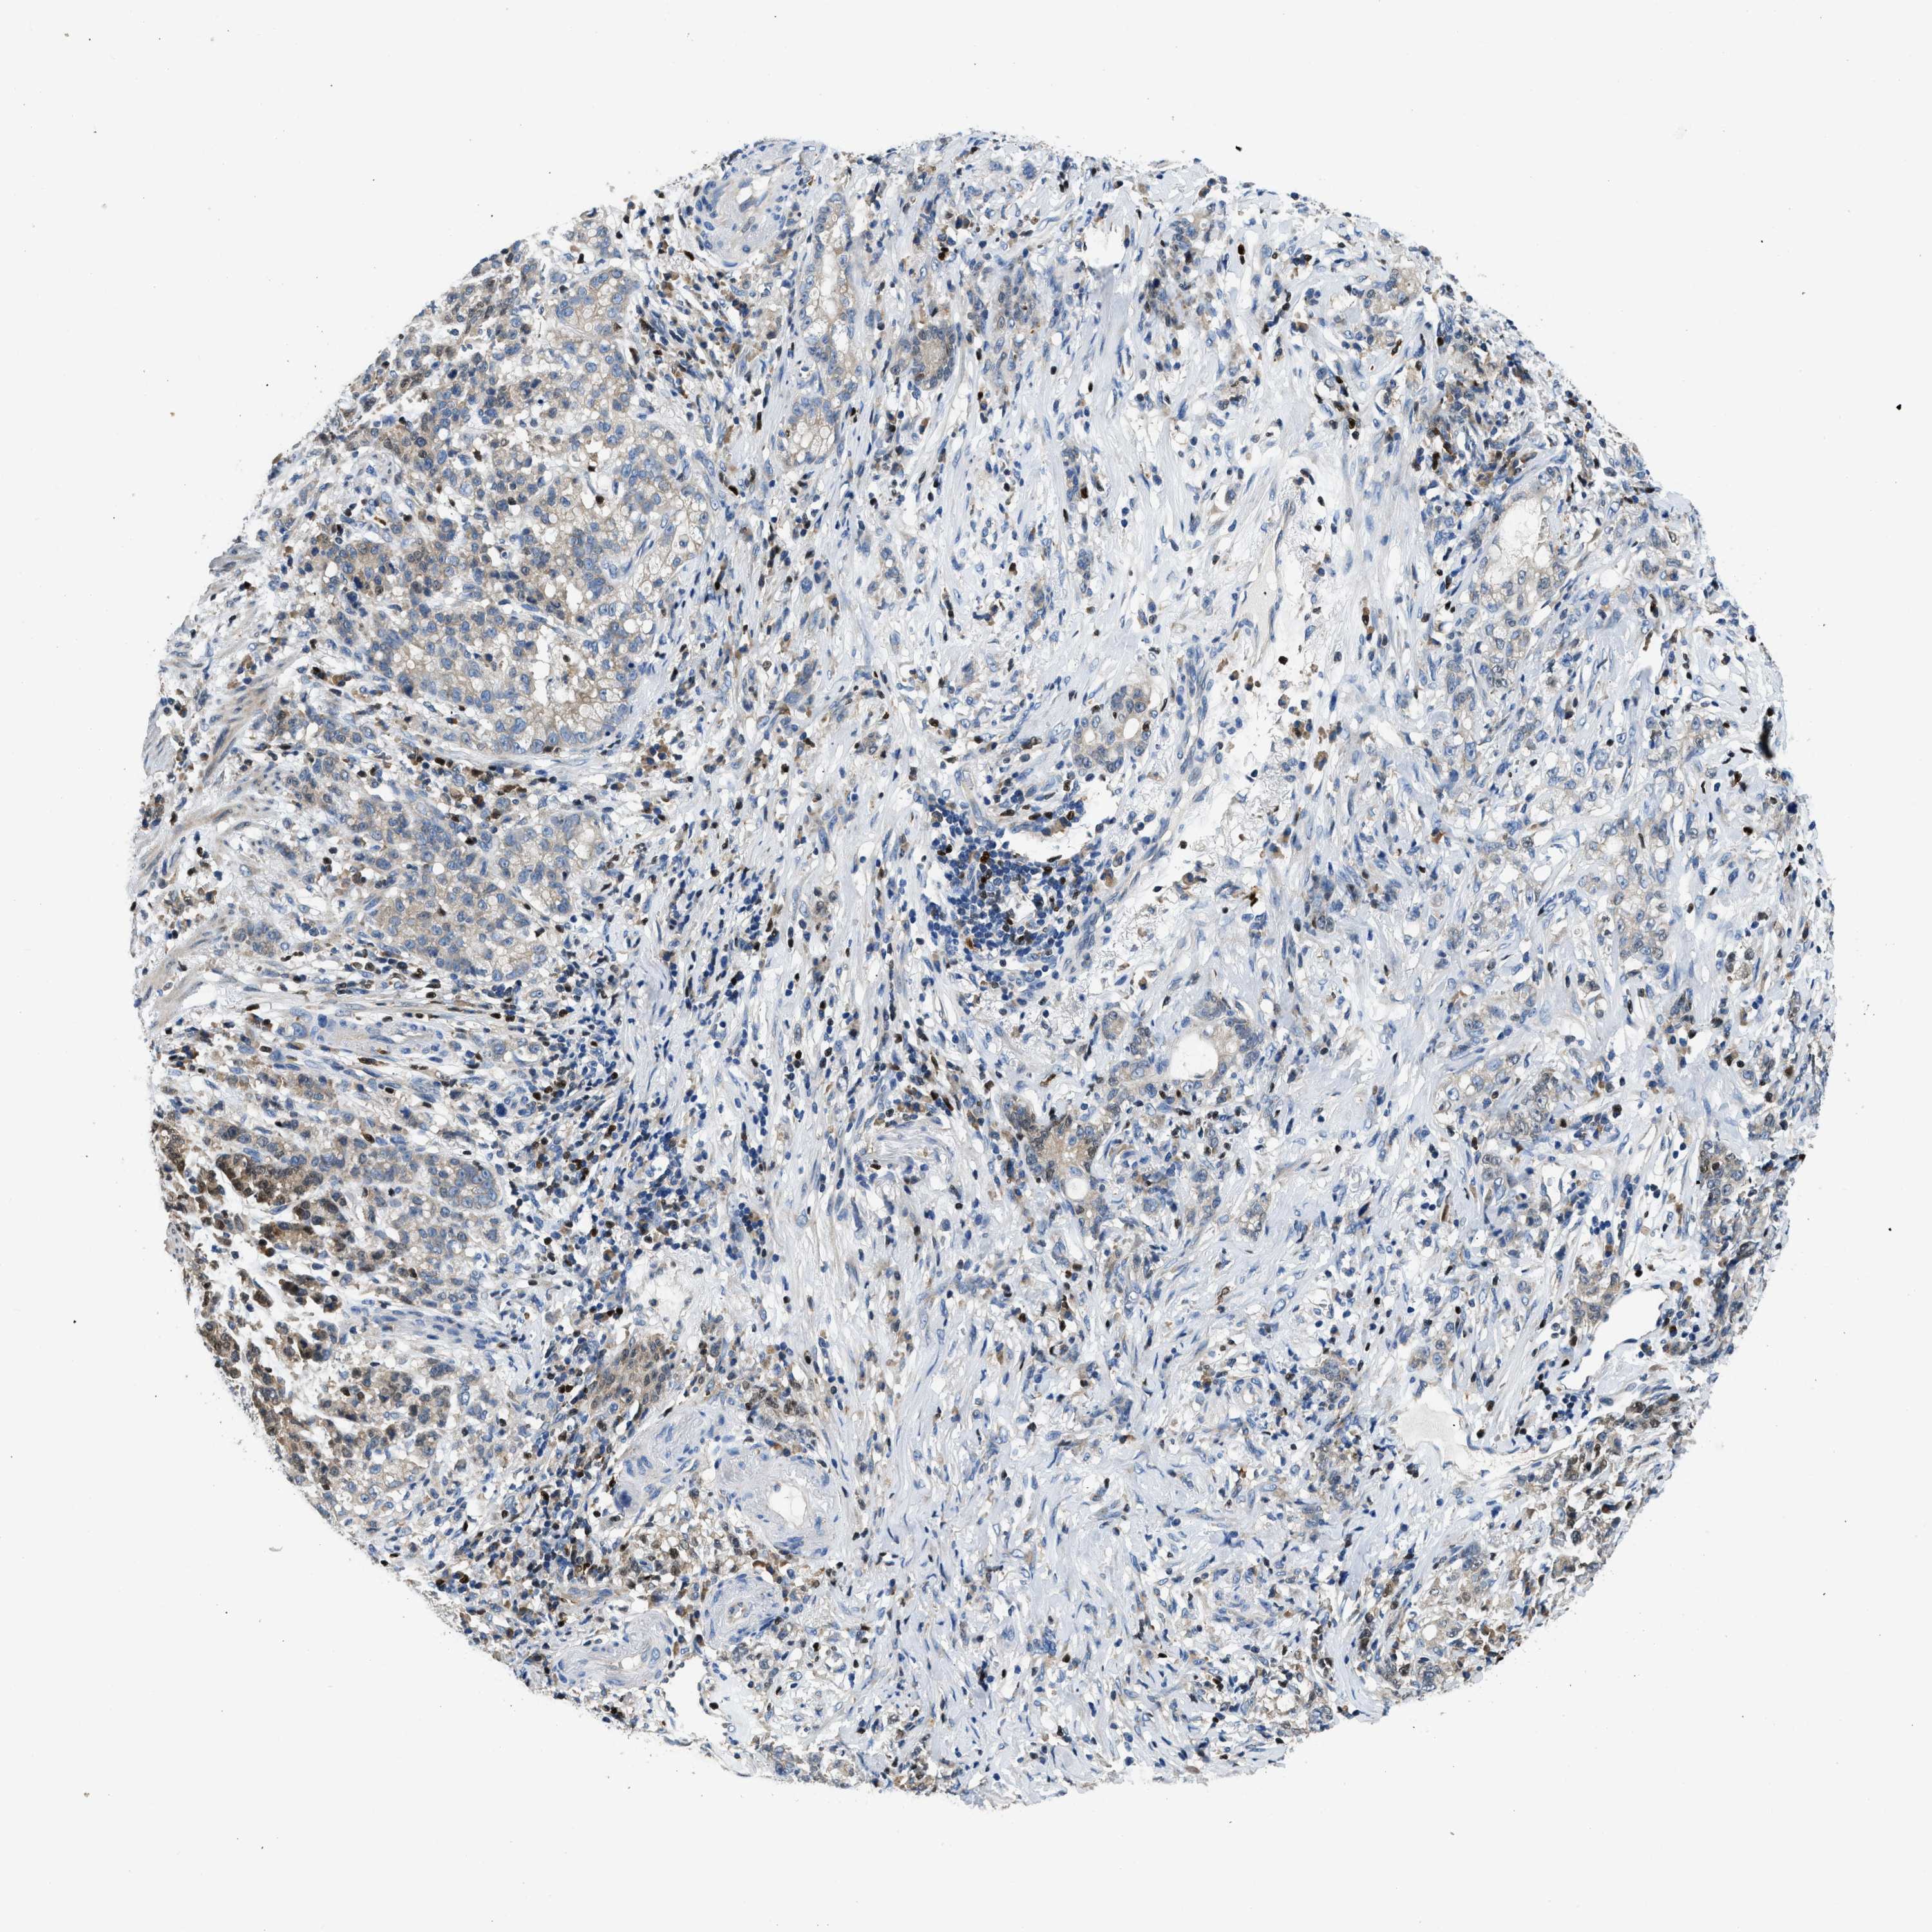

STOMACH CANCER - Protein expressioni

A mouse-over function shows sample information and annotation data. Click on an image to view it in a full screen mode. Samples can be filtered based on level of antibody staining by selecting one or several of the following categories: high, medium, low and not detected. The assay and annotation is described here.

Note that samples used for immunohistochemistry by the Human Protein Atlas do not correspond to samples in the TCGA dataset.

Antibody stainingi

Antibody staining in the annotated cell types in the current human tissue is reported as not detected, low, medium, or high, based on conventional immunohistochemistry profiling in selected tissues. This score is based on the combination of the staining intensity and fraction of stained cells.

Each image is clickable and will lead to virtual microscopy that enables deeper exploration of all samples and also displays staining intensity scores, fraction scores and subcellular localization as well as patient and tissue information for each sample.

Antibody HPA018322

Staining

High

Medium

Low

Not detected

Intensity

Strong

Moderate

Weak

Negative

Quantity

>75%

75%-25%

<25%

None

Location

Nuclear

Cytoplasmic/membranous

Cytoplasmic/membranous,nuclear

Adenocarcinoma, NOS